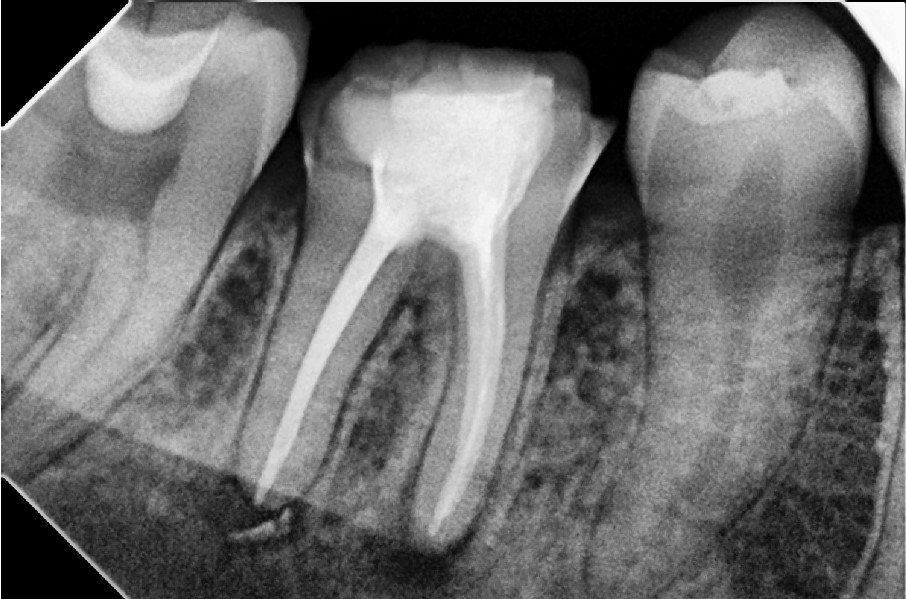

4. Filling the Canals

The clean canals are filled with a biocompatible material called gutta-percha, and sealed to prevent reinfection.

5. Restoration

The tooth is then sealed with a temporary or permanent filling. In most cases, a crown is recommended afterward to strengthen and protect the treated tooth, especially in the back of the mouth.